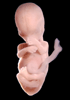

Carnegie Stage 23 (56 post-ovulatory days)

Most embryos at stage 23 are approximately 56-57 postovulatory days old and measure 23-32 mm in length. Distinguishing criteria for this stage include fusion of the eyelids at the medial and lateral margins, clear distinction of the subdivisions of the upper and lower limbs, the forearms appear at or above the level of the shoulders, the superficial vascular plexus of the head is very close to the vertex, and the external genitalia are well developed but not always sufficiently to distinguish the embryo's sex.

(NOTE: These specimens are late stage 23.)